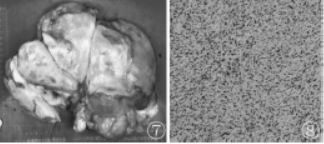

行腹膜后肿块切除术,术中见右侧腹膜后巨大囊实性肿物,上部质硬,似有假包膜,肿物下部部分呈囊性。

图7 肿物表面切面部分区域呈实性,切面灰黄质硬;图8 病理(HE,×200)显示肿瘤细胞明显多形性,部分区域呈细胞梭形

免疫组化:CK(-)、Vimentin(+)、EMA(部分+)、Desmin(部分+)、Actin(-)、SMA(-)S100(-)、MyoD1(部分胞浆+)、Myogenin(-)、CD34(部分梭形细胞+)、ERG(-)、Caldesmon(部分-)、FLI-1(部分+)、Ki-67(约30%+)、CD163(部分+)、CD68(部分+)。病理诊断:结合免疫组化,考虑多形性未分化肉瘤(un-differentiated pleomorphic